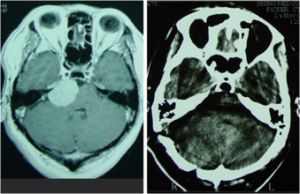

(3)CT①一般可發現直徑3mm以上的腫瘤,顯示鈣化、骨骼、脂肪和液體效果好,有助於了解腫瘤同腦室、腦池、硬膜和顱骨的關係,增強後可了解腫瘤對血-腦脊液屏障的破壞情況和腫瘤的血供。②螺鏇CT的冠狀位和矢狀位重建、三維成像、分割成像和CT血管造影效果更佳。③等密度、小體積、不伴瘤周水腫且無明顯占位效應的腫瘤在CT上可能漏診。④直接徵象,包括腫瘤密度、位置、大小、形狀、數目及邊緣,有無壞死、囊變、出血、鈣化及強化。⑤間接徵象,包括腫瘤周圍水腫、占位表現(腦室、腦池、腦溝的狹窄、變形和移位)、骨質改變(腦膜瘤的骨質增生和破壞,垂體瘤的蝶鞍擴大和破壞,前庭神經施萬細胞瘤的內聽道擴大)和軟組織腫塊等。

(4)磁共振成像一般需先平掃再增強掃描。①腫瘤的部位腦實質外腫瘤以廣基與顱骨內面緊貼,鄰近腦組織受壓且與腫瘤界限清楚,鄰近的蛛網膜下腔或腦池增寬,可有鄰近骨質改變。②腫瘤的信號多數腫瘤為長T1低信號和長T2高信號,脂肪瘤、顱咽管瘤、膠樣囊腫可為T1WI高信號,畸胎瘤T1WI為高、低混雜信號;信號強度均勻者多為良性腫瘤,不均勻者多為惡性腫瘤。③腫瘤的形態凸面腦膜瘤呈球形、顱底腦膜瘤呈盤狀、施萬細胞瘤呈啞鈴狀、脂肪瘤呈條狀。④腫瘤的邊緣。⑤腫瘤的結構結構均勻多為良性病變,信號混雜多為惡性病變;鈣化、出血(MRI對亞急性後期的小出血及其敏感,T1WI為高信號)、壞死、囊變(液面性囊變多見於惡性腫瘤)也可使信號不均勻。⑥腫瘤的數目多發性腦膜瘤、雙側聽神經瘤等常與遺傳性神經腫瘤綜合徵相關,不同部位、不同大小的實質內病灶常提示轉移性腫瘤。⑦腫瘤的增強增強的有無及強弱表示血-腦屏障是否被破壞及其破壞程度,以及腫瘤的血供情況;增強的範圍不一定表示腫瘤的實際大小,特別是腦實質內浸潤性生長的腫瘤;腦實質外的腦膜瘤、施萬細胞瘤常顯著增強。⑧腫瘤周圍水腫MRI對水腫的顯示優於CT;T1WI為低信號,T2WI為高信號;惡性膠質瘤水腫常明顯,可通過胼胝體累及對側半球;轉移瘤也常引起明顯水腫。⑨占位效應。⑩繼發改變。